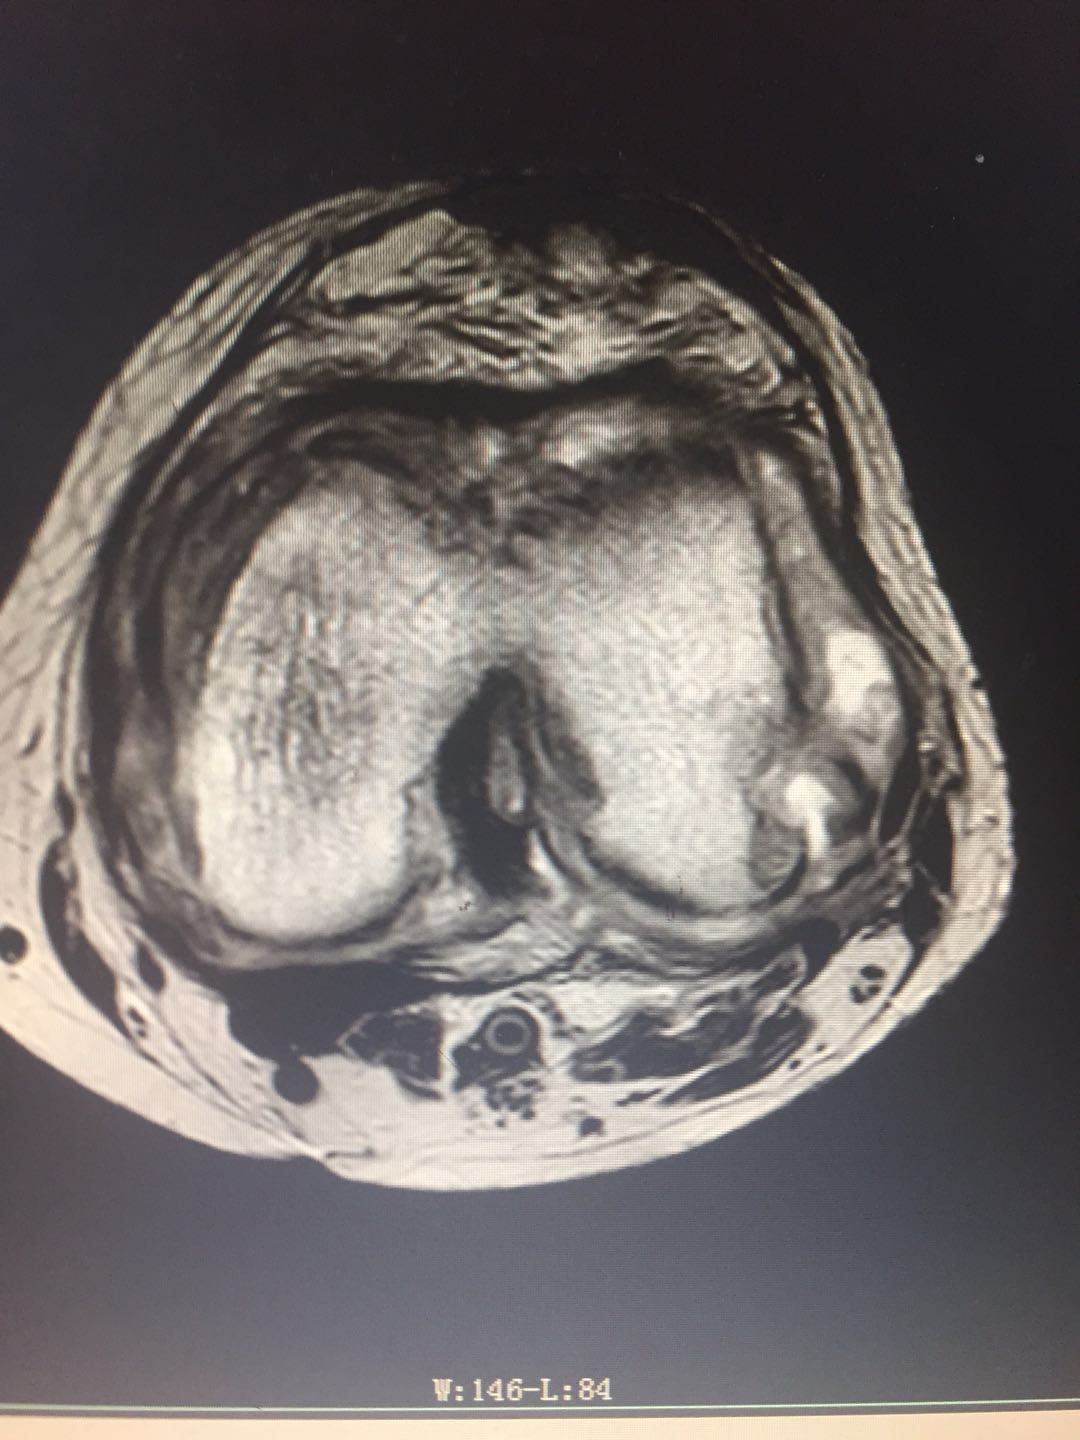

患   者:曾某某 ,女,69岁。

主   诉:左膝疼痛、肿胀、活动受限2年,加重3月,入院治疗。

既往史:2018年6月诊断为“左膝滑膜炎并关节积液”,予关节腔穿刺、理疗、药物治疗后病情好转。无明显潮热、盗汗。

专科检查:左膝部皮温稍增高,皮肤无发红,中度肿胀,呈屈曲位,内侧膝关节间隙处压痛明显,屈伸活动受限,被动活动时疼痛加重,左膝浮髌试验阳性,侧方挤压试验阳性,研磨试验阳性,抽屉试验阴性,肢端觉血运尚可,左下肢肌力感觉未见明显异常。

辅助检查:血沉:37mm/h,C反应蛋白:75.8ng/L,结核杆菌:阴性,降钙素原正常。余检查未见明显异常。

影像资料:

诊        断:

左膝骨性关节炎(K-L分级 4级);

左膝关节滑膜炎并关节积液。